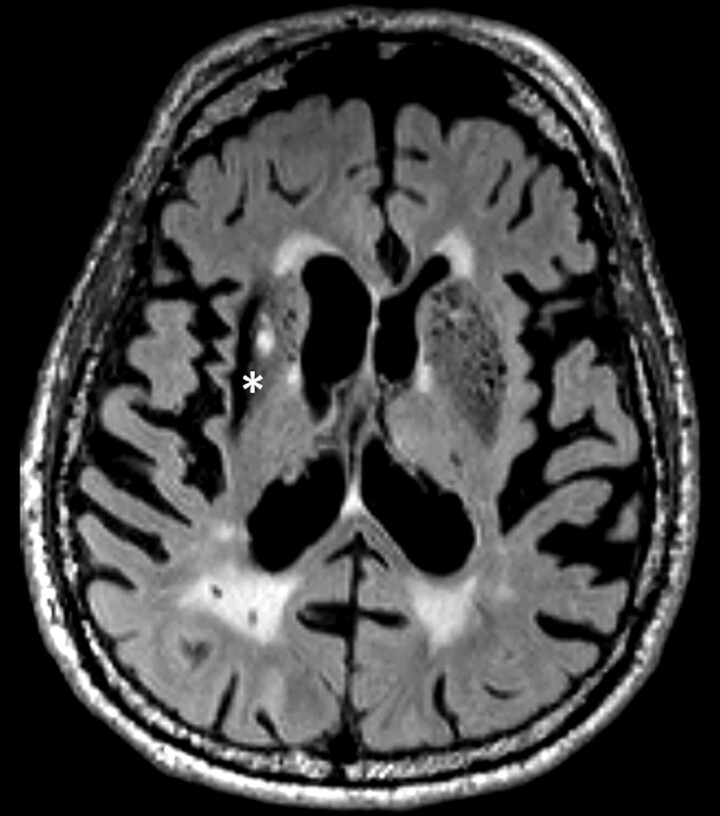

Abb. 69.3 Parkinson-Syndrome: Differenzialdiagnose subkortikale vaskuläre Enzephalopathie.

87-jähriger Mann mit Parkinson-Syndrom . ARWMC-Skala: White Matter 3 (diffus konfluierend) / Basalganglien 2 (mehr als eine fokale Läsion).

a T2w FLAIR-MRT-Sequenz. Fortgeschrittene subkortikale vaskuläre Enzephalopathie mit konfluierenden Marklagerläsionen im Centrum semiovale beidseits.

b Axiale Reformatierung einer 3-D-FLAIR-MRT-Sequenz. Zusätzliche Lakune im Putamen rechts sowie Narbe nach intrazerebraler Blutung im lateralen Putamen rechts. Der Stern kennzeichnet den strichförmigen Blutungsdefekt im Putamen.